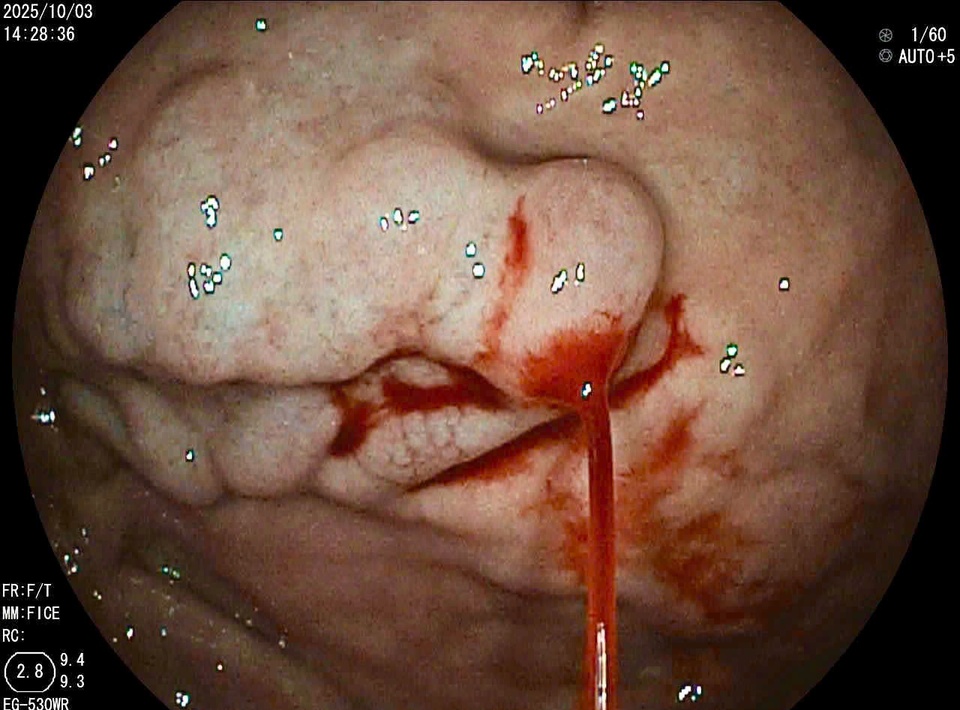

Trong quá trình nội soi, ê-kíp phát hiện tĩnh mạch phình vị giãn độ 3 (IGV1), có điểm vỡ đang phun máu thành tia. Ảnh: BVCC.

Theo bác sĩ Hà Văn Kim, Trung tâm Nội soi tiêu hóa và Thăm dò chức năng, Bệnh viện Bệnh Nhiệt đới Trung ương, trong quá trình nội soi, ê-kíp phát hiện tĩnh mạch phình vị giãn độ 3 (IGV1), có điểm vỡ đang phun máu thành tia. Ngay lập tức, đội ngũ bác sĩ thực hiện kỹ thuật tiêm xơ búi giãn bằng dung dịch Histoacryl và Lipiodol, giúp cầm máu hoàn toàn chỉ sau vài phút.